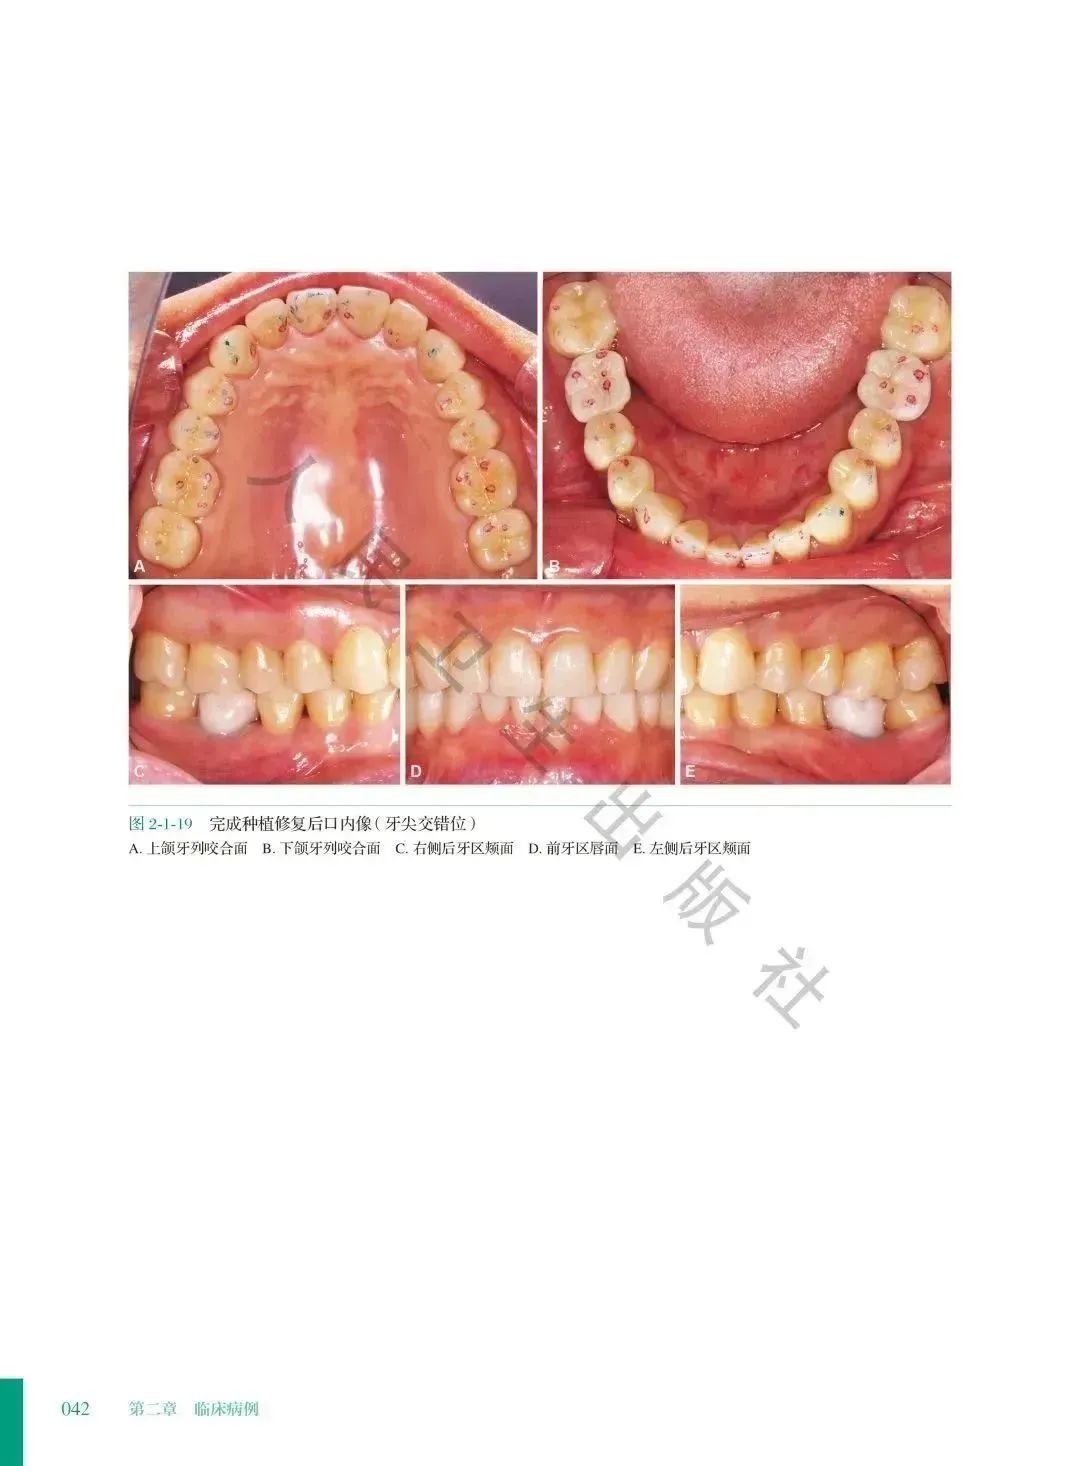

②. 本册收录短面型病例,临床最多见的是前牙磨损。这类病例具有共同的临床特征,可以详细说明治疗方法的共性;每个病例又针对患者各自的特点做了相应的调整,各有侧重。